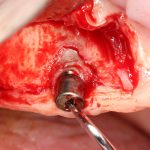

Прежде, чем приступить к аугментации (пластике) лунок зубов, мы подготовили лунки для имплантатов. В таких клинических случаях нет необходимости в использовании шаблона. Вместо этого, мы применяем общепринятые правила позиционирования и соблюдаем рекомендации производителя по хирургическому протоколу:

В процессе ирригации лунки промываются, что позволило нам еще раз подтвердить ранее сделанные выводы. С помощью аналогов имплантатов, входящих в хирургический набор Xive, мы проверили возможность стабилизации имплантатов в будущих лунках. Исходя из правил подбора и позиционирования имплантатов (я очень рекомендую почитать об этом здесь>>) мы остановились на Xive S диаметром 3,4 мм и длиной 13 мм.